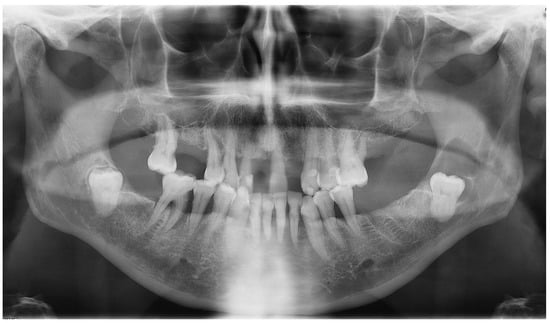

The oral clinical examination was unremarkable, and the patient was asymptomatic. On the OPG, a pericoronary radio-transparent lesion around impacted tooth #38 was discovered (Figure 8). The involved tooth was oriented mesially. The lesion was poorly delimited, measured 24 × 10 mm, and stretched to the apparently resorbed distal root apex of tooth #37. The roots of tooth #38 clearly overlapped with the IAC, raising suspicion of interference. The OPG images were indicative of a DC with possible secondary infection and perilesional sclerosing osteitis.

The complementary CBCT examination found that tooth #38 was directed mesially and slightly lingually (Figure 9) and that it had three roots, with the deformed IAC tortuously passaging between them. The crown of tooth #38 was close to the distal root of tooth #37, whose apex was strongly resorbed. The pericoronal osteolytic lesion measuring 24 × 10 × 10 mm extended from the crown-root junction of tooth #38 to the partially resorbed distal root of tooth #37. There was bone dehiscence of 12 mm on the alveolar crest and of 5 mm on the vestibular cortex. The borders of the lesion were in places irregular and strongly sclerotic, indicating a superimposed infection. There were no signs of bone sequestration, periosteal reaction or associated fracture. These findings supported the initial diagnosis of DC.